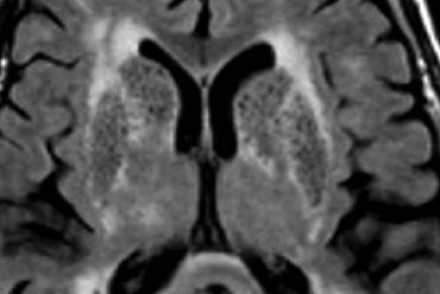

Слева на Т2-взвешенной томограмме видны множественные очаги высокой интенсивности в области базальных ганглиев. Справа в режиме FLAIR сигнал от них подавляется, и они выглядят темными. На всех остальных последовательностях они характеризуются такими же характеристиками сигнала, как ликвор (в частности, гипоинтенсивным сигналом на Т1 ВИ). Такая интенсивность сигнала в сочетании с локализацией описанного процесса являются типичными признаками пространств Вирхова-Робина (они же криблюры).

Пространства Вирхова-Робина окружают пенетрирующие лептоменингеальные сосуды, содержат ликвор. Их типичной локализацией считается область базальных ганглиев, характерно также расположение вблизи передней комиссуры и в центре мозгового ствола. На МРТ сигнал от пространств Вирхова-Робина на всех последовательностях аналогичен сигналу от ликвора. В режиме FLAIR и на томограммах, взвешенных по протонной плотности, они дают гипоинтенсивный сигнал в отличие от очагов иного характера. Пространства Вирхова-Робина имеют небольшие размеры, за исключением передней комиссуры, где периваскулярные пространства могут быть больше.

На МР-томограмме можно обнаружить как расширенные периваскулярные пространства Вирхова-Робина, так и диффузные гиперинтенсивные участки в белом веществе. Данная МР-томограмма превосходно иллюстрирует различия между пространствами Вирхова-Робина и поражениями белого вещества. В данном случае изменения выражены в значительной степени; для их описания иногда используется термин «ситовидное состояние» (etat crible).

Пространства Вирхова-Робина увеличиваются с возрастом, а также при гипертонической болезни в результате атрофического процесса в окружающей ткани мозга.